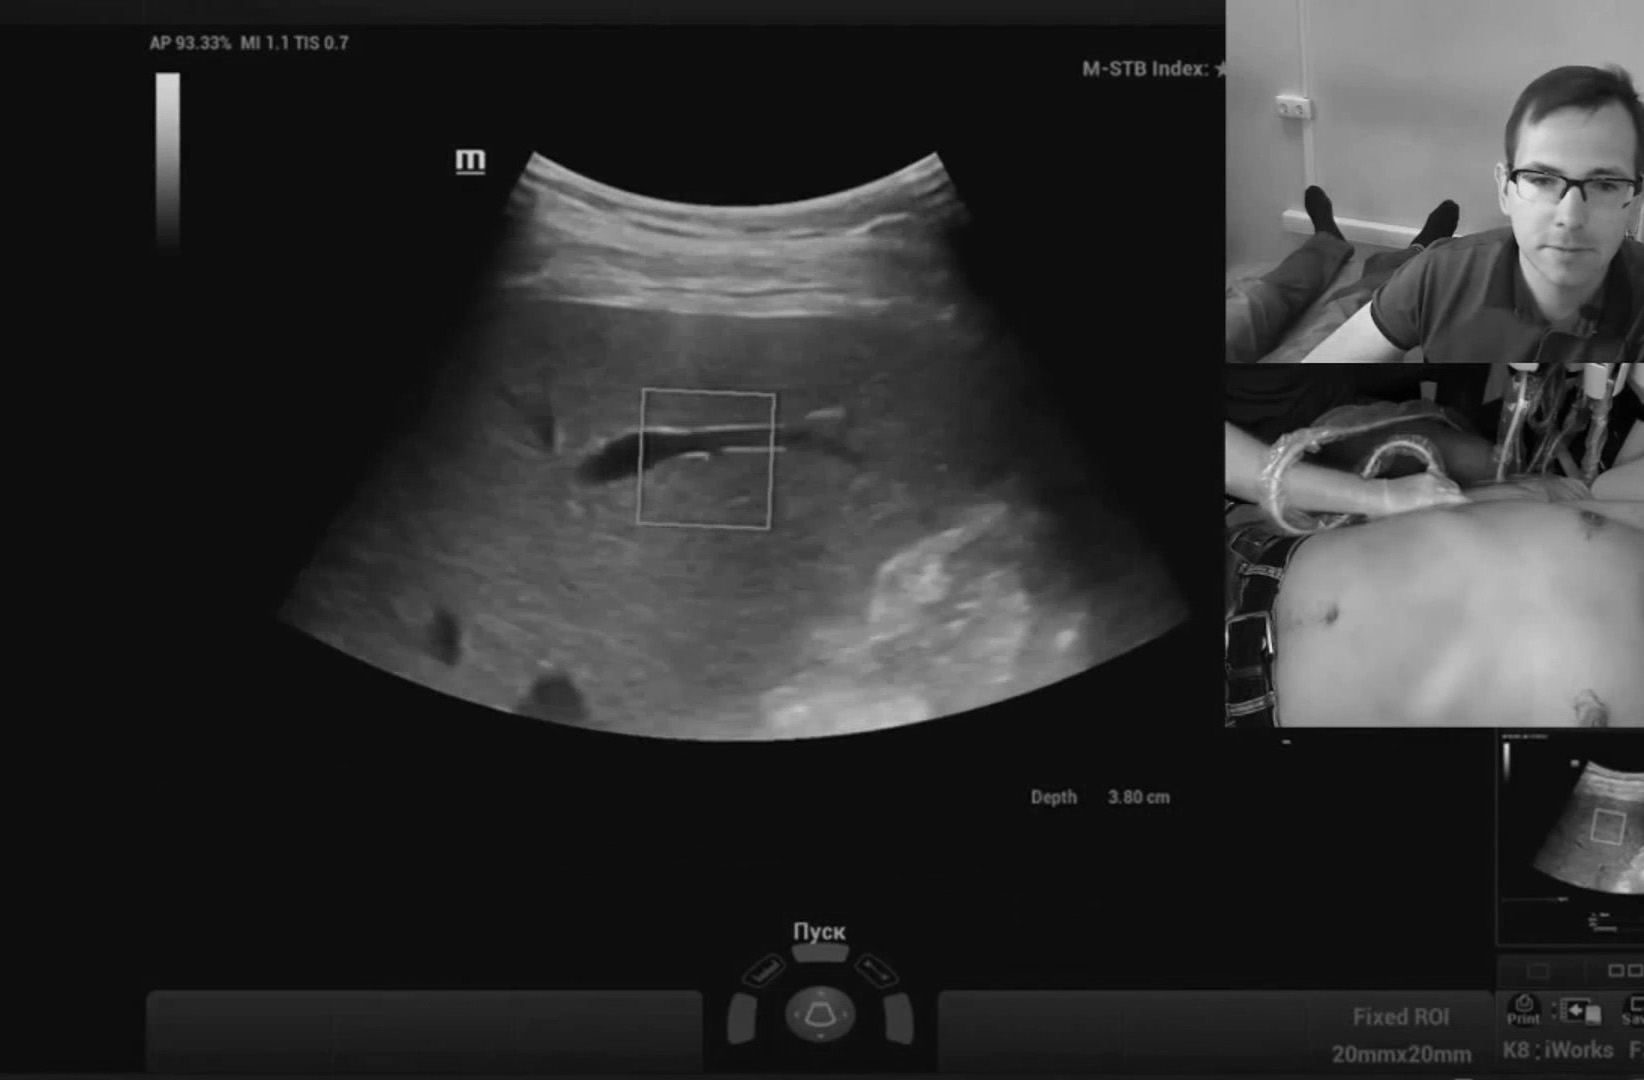

Работа с видео петлями реализована в полном объеме, то есть можно снять видео без оптимизации и отпустить пациента, оптимизацию провести уже на отснятых петлях в удобное время. Наличие эластографии сдвиговой волны периодически заставляет забыть, что я врач УЗД, бывают дни, когда делаешь одну эластографию печени. Очень популярная методика.

Обзор УЗИ: Отзыв о работе ультразвукового аппарата Mindray Resona 6

«Первое, на что обращаешь внимание, это очень чувствительный допплер. Пациентов с плохим эхо-окном на височном доступе ТКДГ просто не было за все время работы, мозговые артерии видны всегда. Для поиска камней в почках допплеровский мерцающий артефакт также работает отлично, удавалось находить камни от 0.7 мм именно по мерцающему артефакту.

Большим плюсом для меня, как для врача диагноста, является открытый калькулятор, я могу внести любые новые измерения и формулы. Таким образом, прибор считает всё, я не сижу с листочками и не считаю ничего вручную. Работа с В-режимом за счет корректировки константы распространение ультразвуковой волны сильно упрощается, поджелудочная видна сразу и целиком в 99% случаев.

Осмотр брюшной полости в педиатрии линейным датчиком с низкими частотами - без проблем, сигнал не затухает. Живот просвечивает насквозь, стенки кишечника и желудка видны четко и детально. Поиск лимфоузлов брыжейки - без проблем. Кардиопакеты полные с возможностью стрейна, тканевого допплера, авторасчета объема и фракции выброса желудочков. Измеряемые объемы автоматически индексируются на площадь поверхности тела.

Список возможных расчетов огромен, можно настроить меню калькулятора под себя, какими пользуюсь. Разброс частот на фазированном датчике довольно большой, что позволяет смотреть как новорождённых, так и взрослых. По сонным артериям также без проблем, проникающая способность шикарная, чувствительность допплера шикарная, авто-настройка допплера - вплоть до угла сканирования. Анализ стабильности бляшек по системе GSM уже встроен, надо только вынести его в меню расчетов».